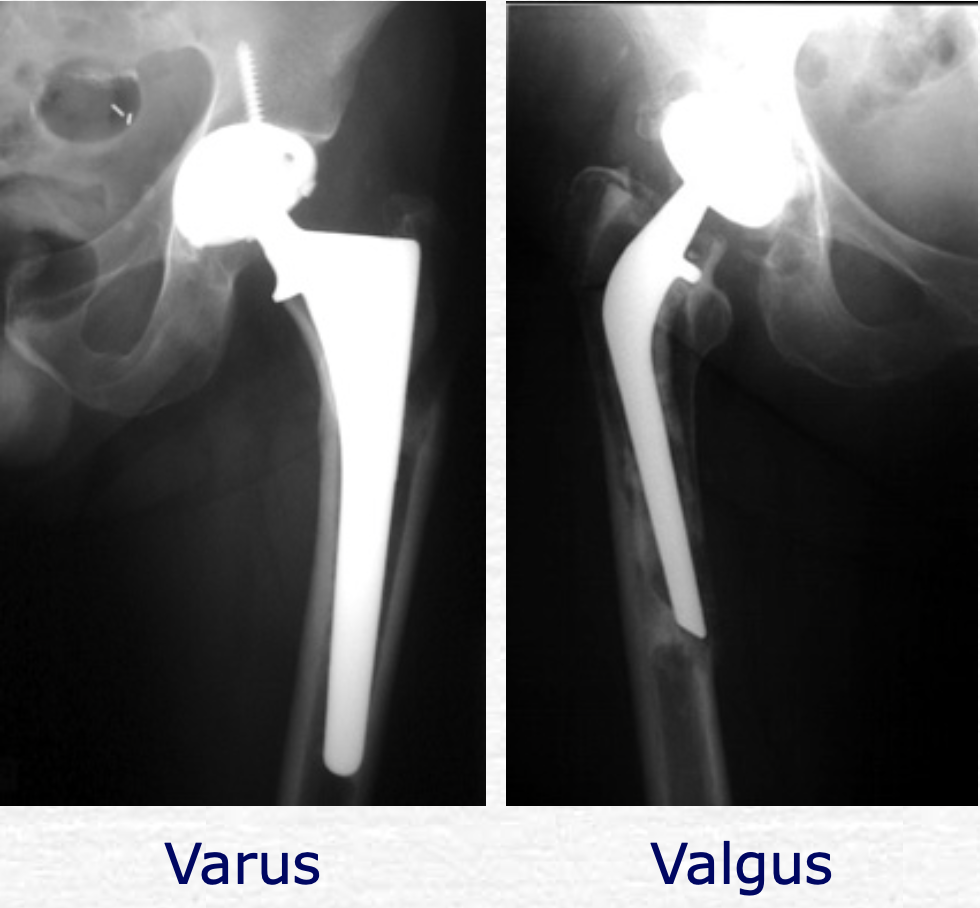

현재 main으로 사용되는 디자인은 Collarless, polished, and tapered stem 입니다.